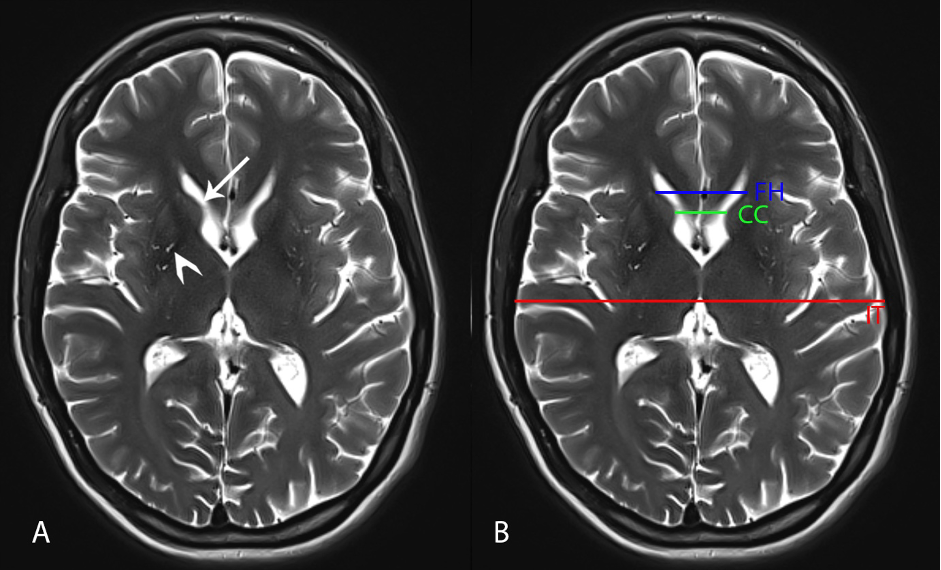

Results: Brain MRI showed a subjectively reduced volume of the caudate nuclei (arrow pointing to the right caudate nucleus) and putamina (arrowhead pointing to the right putamen) Axial T2-weighted image (Figure 1 A) and frontal horn width (FH)/intercaudate distance (CC) was 2.06 which is low. While the CC/inner table width (IT) ration was 0.13 which is elevated (Figure 1B). Genetic testing revealed 48 and 16 CAG repeats, with the 48-repeat allele in the fully penetrant range for Huntington’s Disease (HD). Patient received more social support and symptoms are managed by Valbenazine, clonidine, fluphenazine, duloxetine.

Figure 1: Brain MRI